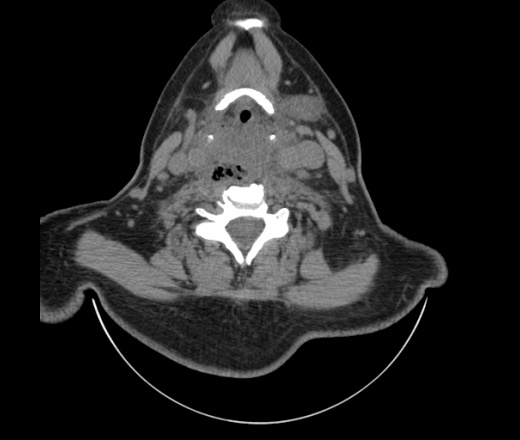

Женщина поступила в х/о спустя 4 дня после того как при употреблении карася подавилась костью.

Наличие газа в средостении на протяжении тел С2-С6 (медиастинальна эмфизема); рыбная кость на уровне тела С6.

При всем уважении, но говорить о медиастинальной эмфиземе, оценивая мягкие ткани шеи, как-то слишком резко. На мой взгляд, это ретрофарингеальное пространство.

Эвакуировали почти 100мл гноя. Но кость не смогли найти. Думаю что она даст дальнейшее ослоднение. Эндоскопически за черпалонадгортаной звязкой не смогли зайти в пищевод, все мягкие ткани отечные, просвет пищевода сдавлен. По всей видимости параэзофагеальная клетчака тоже задействована. Эмпиема, если ее можно так назвать, незнаю как правильно дошла до уровня яремной вырезки. Чем закончиться напишу. Ждем медиастинита.

Флегмона заглоточного пространства шеи, только операция, флегмоны вскрывают. Риск медиастинита.

Согласен с Вами; конечно, наличие газа в клетчатке ретрофарингеального пространства (затмение с опечаткой..). К сожалению, процесс "продвигается" к медиастиниту. Но почему никто, не отмечает наличие рыб. кости; или это для Всех очевидно?

Так вы уже отметили. Хотя ориентировал бы не скелетотопически, а на перстнечерпаловидный сустав.

Кость то мы сразу выявили, размеры где то 17*2мм, но ее так и не получается найти в этой каше